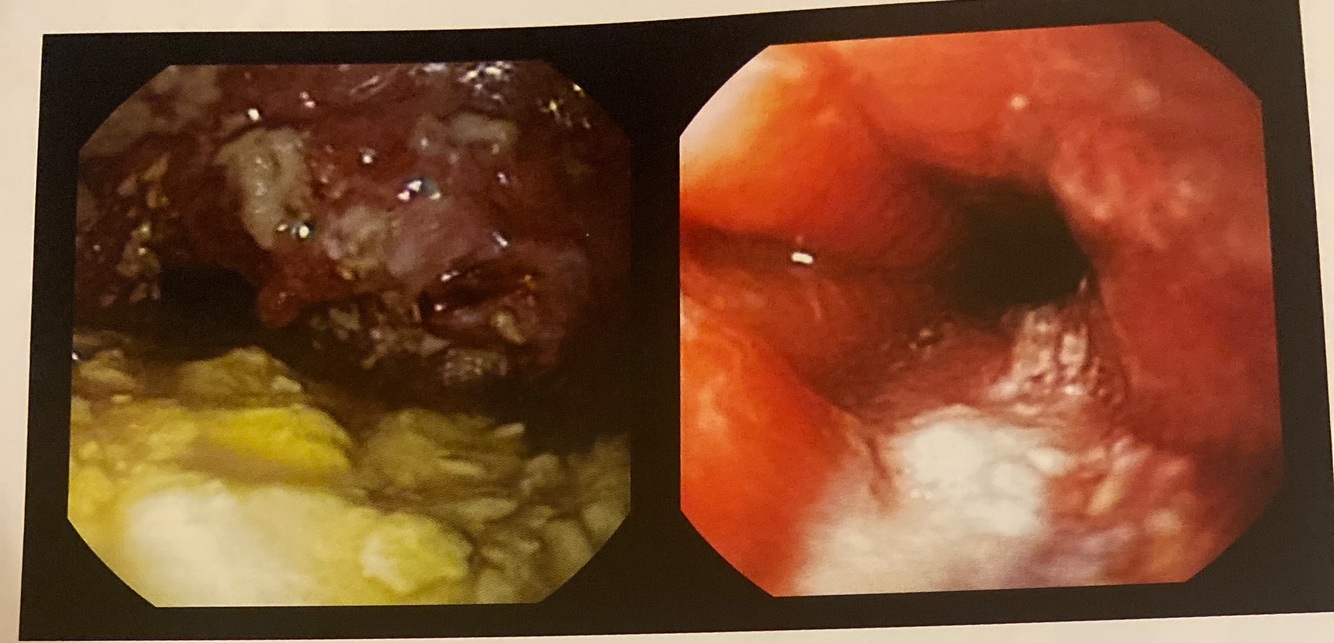

Esôfago

Câncer esofágico